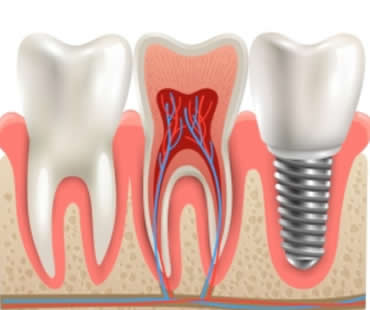

Introducing Dental Implants

The Many Benefits of Dental Implants

Dental Implants: Choosing the Best Implant Dentist in Shelby Township

When to Choose Mini Dental Implants

Benefits of Dental Implants